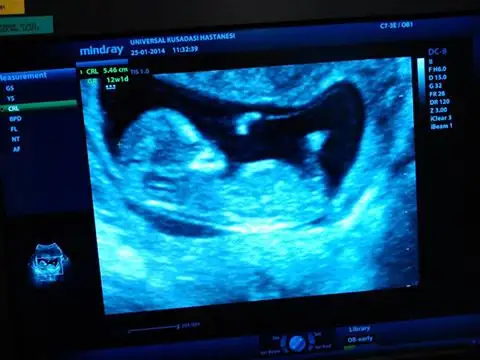

zeynepcim 12 haftalık bu resimde bebişim bu cuma 16 olcaz 7 yaşında kızım var kızları çok sevsemde bu farklı olsun istiyo insan benim resmide face ye koyarmısın birde face adınız ne bende bakayım $1624209_10202220567127945_1171059103_n.webp

12 haftalık bebebiğim..ben birsey anlayamadım.kız yada erkek bir tahmini olan var mı..